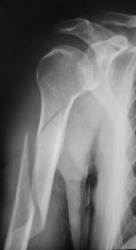

Травма. Пациент направлен врачом хирургом на рентгенографию плечевого сустава.

Что посоветуете уважаемые коллеги?

Спиральный перелом со смещением. А что в локтевом суставе? Мне кажется, что спираль продолжается дистальнее.